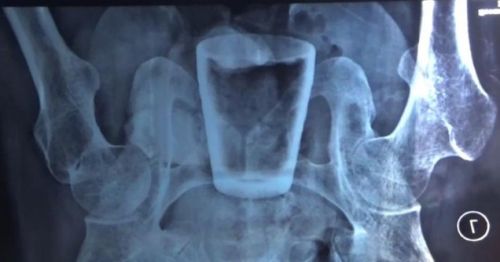

Gelas Kaca dalam Perut Pria Asal Jember, Ini Penjelasan Dokter

07-April-2022 21:32

Geger, Ada Gelas Kaca dalam Perut Pria di Jember

07-April-2022 19:38

Viral, Ada Gelas Masuk ke Perut Pria di Jember

06-April-2022 18:47